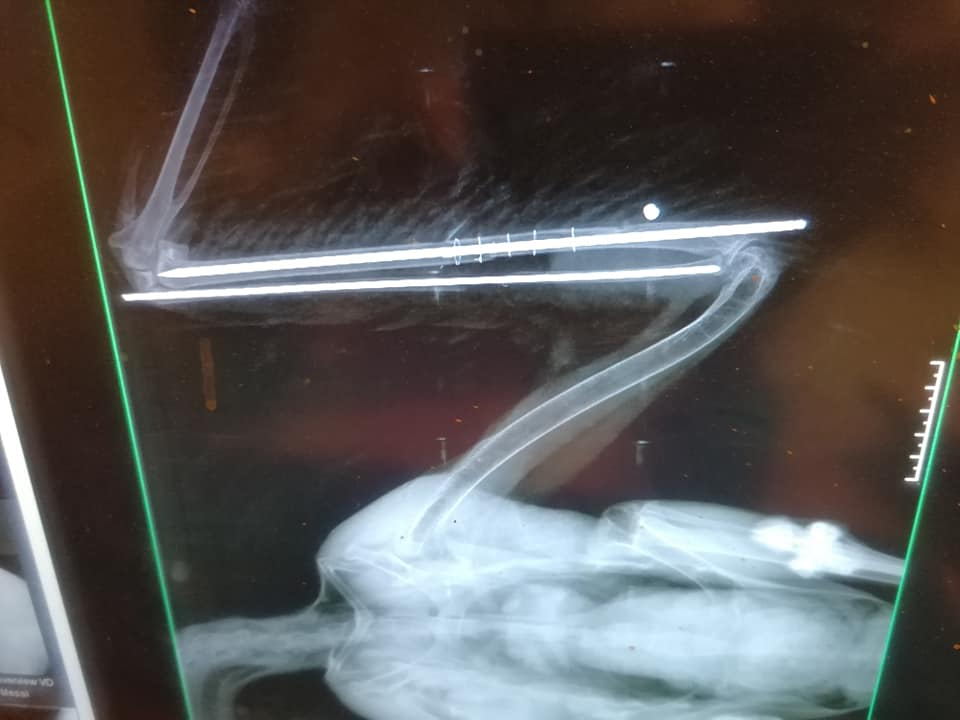

Mint írják, szerdán majdnem egyszerre szállítottak be egy légpuskával meglőtt fehér gólyát (fokozottan védett faj, eszmei értéke 100 ezer forint) és egy szabálytalanul kihelyezett csapóvas által fogott barna rétihéját (védett, eszmei értéke 50 ezer forint). Előbbi valószínűleg fészkel, tojásai jelenleg árván maradtak. A lövedék a madár felkarcsontját roncsolta, gyógyulása több mint 2 hónapig is eltarthat. Utóbbinak a csapóvas majdnem letörte a lábfejét, az állat jelenleg is válságos állapotban van.

Kép forrása.